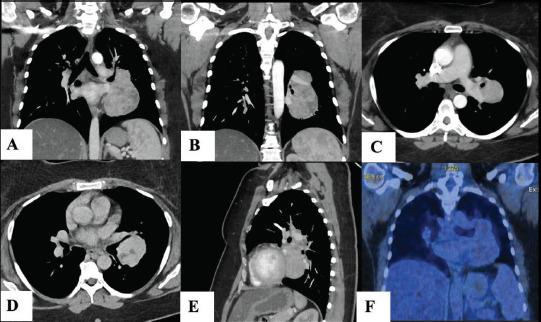

We report the case of a 42-year-old woman who underwent resection of an 11 cm intrapulmonary UCD. Additionally, we conducted a systematic review of the demographics, clinical presentation, diagnosis, and treatment approaches for intrapulmonary UCD.

Our review identified 35 documented cases of intrapulmonary UCD, including our case. The average age was 34 years, with a female predominance of 57.7%. Tumor sizes ranged from 1.5 to 11 cm, with our case being the largest. Of the 24 cases with reported anamnesis, 58.3% were asymptomatic, while 41.7% had nonspecific symptoms such as cough, chest pain, or fever (as in our case). Histological analysis was available for 24 cases, with 83.3% identified as the hyaline vascular type. Biopsies through small needle aspiration or fresh-frozen samples failed in all attempts, requiring resection for diagnosis and treatment. Due to high vascularity, delicate location, and lack of diagnosis, lobectomy or pneumonectomy was performed in 45.7% of cases. Among the 11 cases with reported follow-up, no disease recurrence was observed over an average of 3 years.